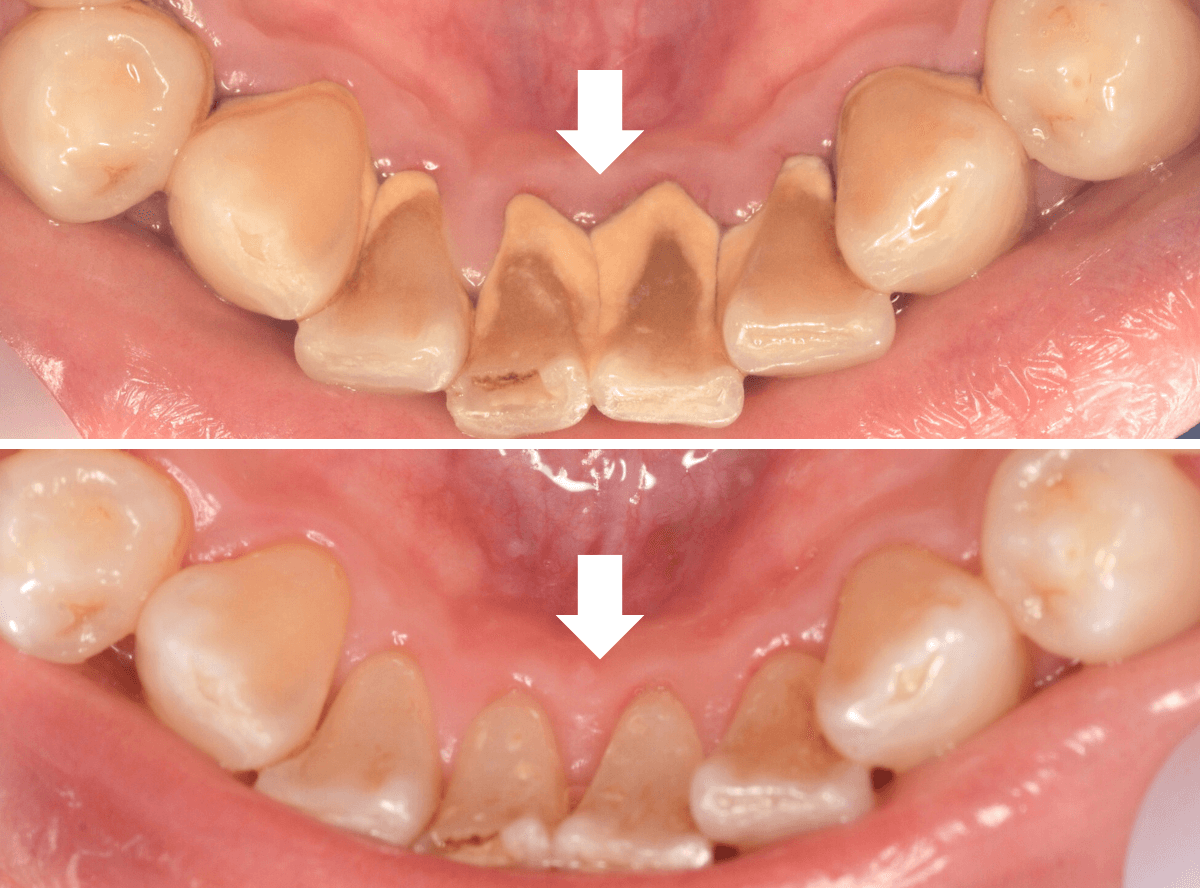

Case.1

「口臭が気になる」という理由で来院された患者さんです。

何度か来院され、歯石除去や歯ブラシ指導をしているのですが、まだまだ、徹底されていないのがわかります、もう少し頑張ってほしい(><)

歯肉の縁が赤く腫れています。こういった歯肉の中には歯石がたまっている可能性が大です。

この歯肉の中の見えない歯石は、歯肉の上の歯石よりも、歯周病の原因になります。

歯周病は痛みなどの自覚症状に乏しく、気づけば完全に治らない状態まで進んでいる事も多いので早期発見・治療が大切です。

保険診療では、歯石除去は一日で治療できる範囲が限られています。

今回は、上の前歯の部分の歯肉の中の歯石除去をしました。

歯石除去後です。

この状態を長く維持してもらう必要があります。

ここまで歯石除去の解説をしましたが、実は歯周病の治療で一番効果のある治療は、患者さんの日々の歯ブラシです。

お部屋のお掃除をイメージしてもらうとわかりやすいかと思います。

歯石除去=業者に頼む大掃除

歯ブラシ=日々の掃除

せっかく歯石除去をしていても、歯ブラシがしっかりできていないと、効果は薄く、元の木阿弥になってしまいます。

患者さんには、今一度、気を引き締めて歯ブラシをしていただくよう指導しました。

どのくらい歯肉が治っていくのか経過観察する必要があります。